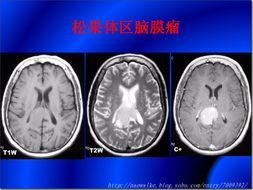

2. MRI下的脑瘤

MRI(磁共振成像)是另一种常用的脑瘤诊断方法。与CT扫描相比,MRI可以更清晰地显示脑瘤的内部结构。在MRI的照片中,脑瘤的颜色和形状更加明显,让人触目惊心。